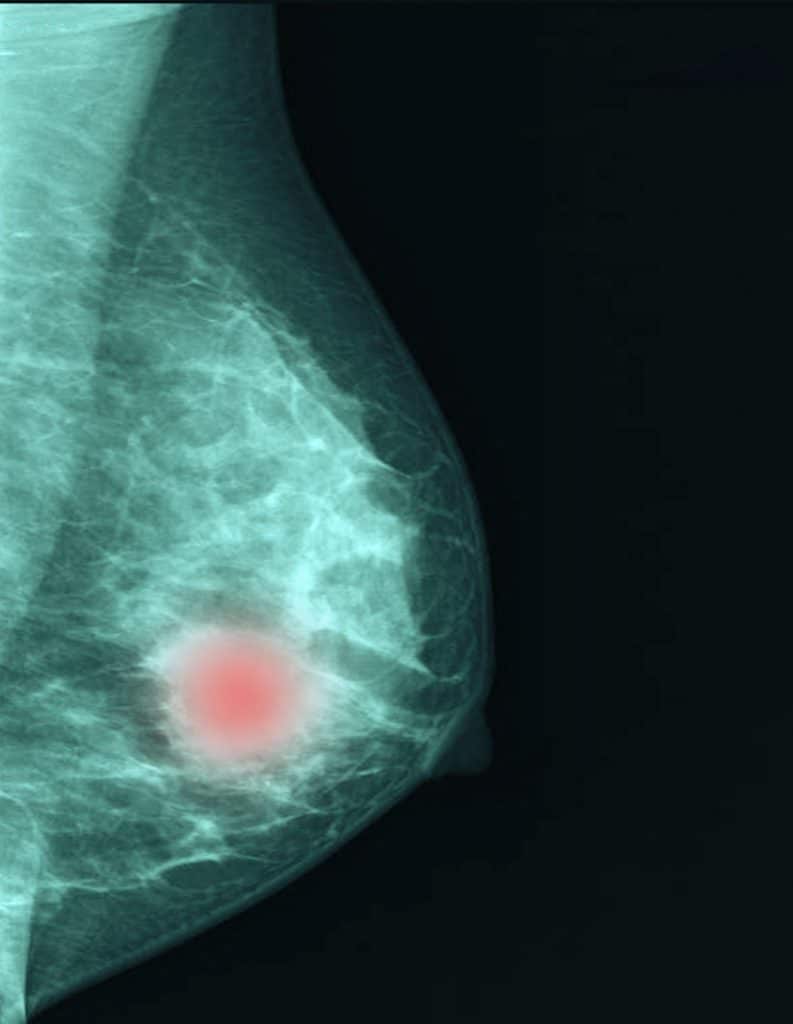

Automatiser la détection du cancer

On peut programmer les ordinateurs afin qu’ils analysent les mammographies de manière à détecter des lésions non visibles à l’œil nu pour dépister plus précocement un cancer du sein. De plus, en comparant les images obtenues avec celles contenues dans d’immenses banques de données, les programmes informatiques pourraient mieux discriminer si une anomalie est réellement une tumeur ou un simple artéfact.